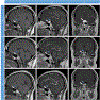

Figures